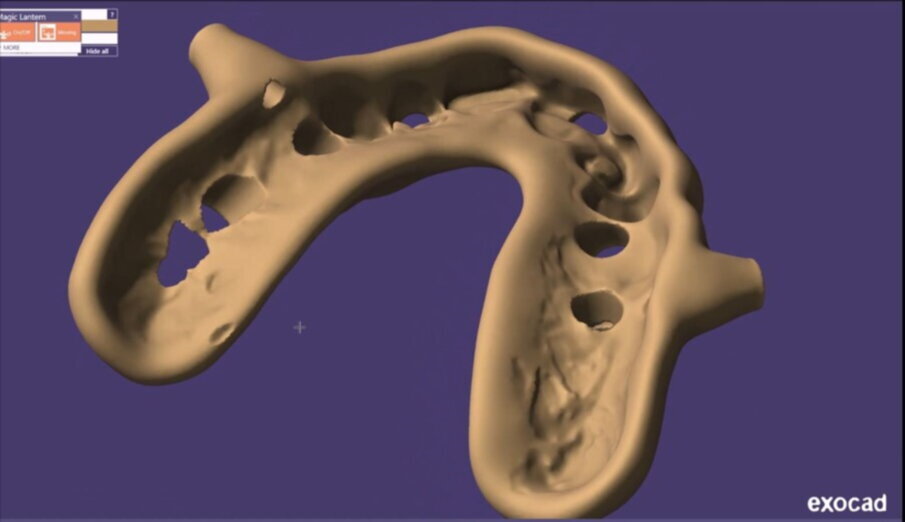

Figg. 13, 14_File STL ottenuti tramite scanner intraorale.

Figg. 21-25_Progettazione Cad con exocad.